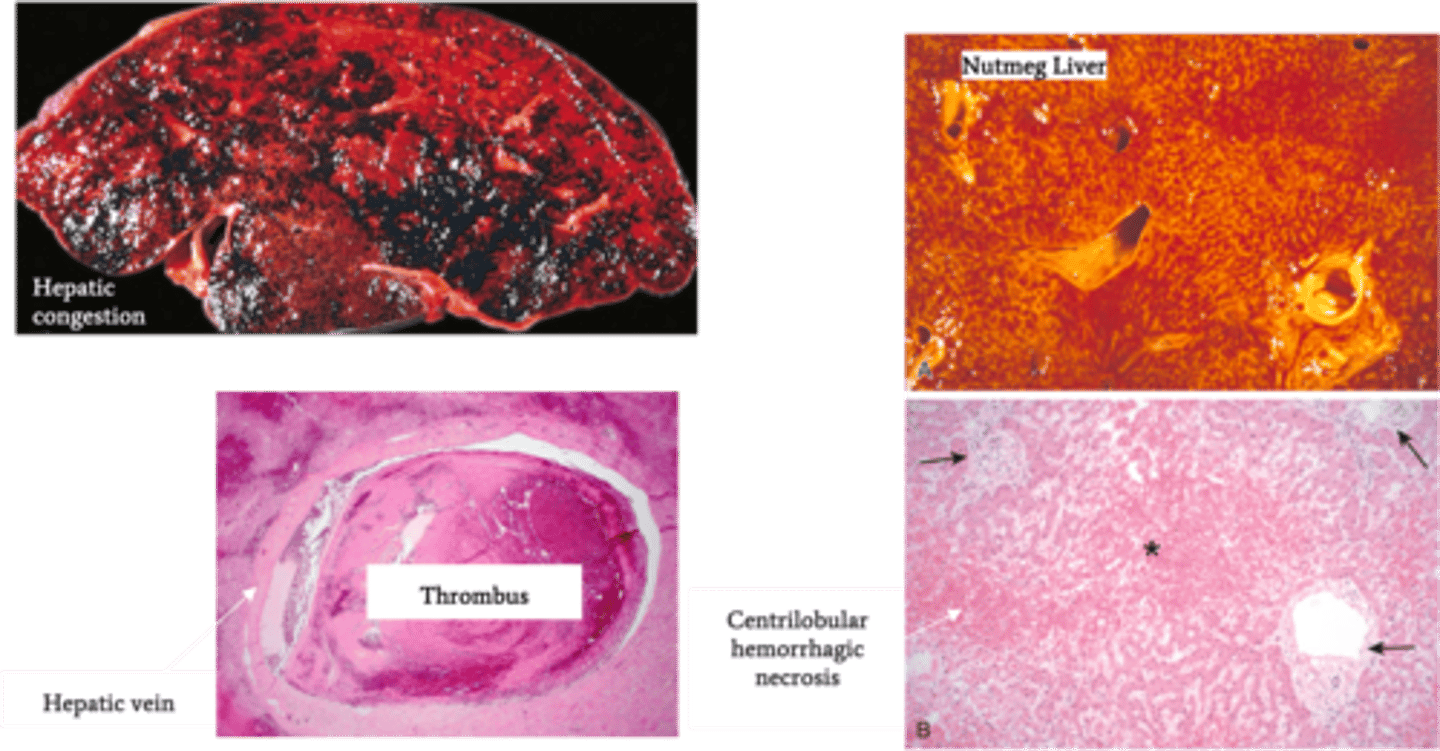

Budd-Chiari Syndrome

Define Condition:

Hepatic venous outflow obstruction d/t thrombosis OR compression of hepatic vein; POST-HEPATIC

-Hx: Hypercoagulable States

> Polycythemia Vera

> HCC

> OCP

> Pregnancy

-Path:

-Sx/PE:

> Abd Pain

> Ascites

> Hepatomegaly

-Dx:

> Gross:

>> Hepatic Congestion

>> Hepatomegaly

>> Tense Capsule

> Biopsy:

>> Severe Centrilobular congestion and necrosis

>> Passive Liver Congestion = NUTMEG LIVER

>> Major veins may have thrombi